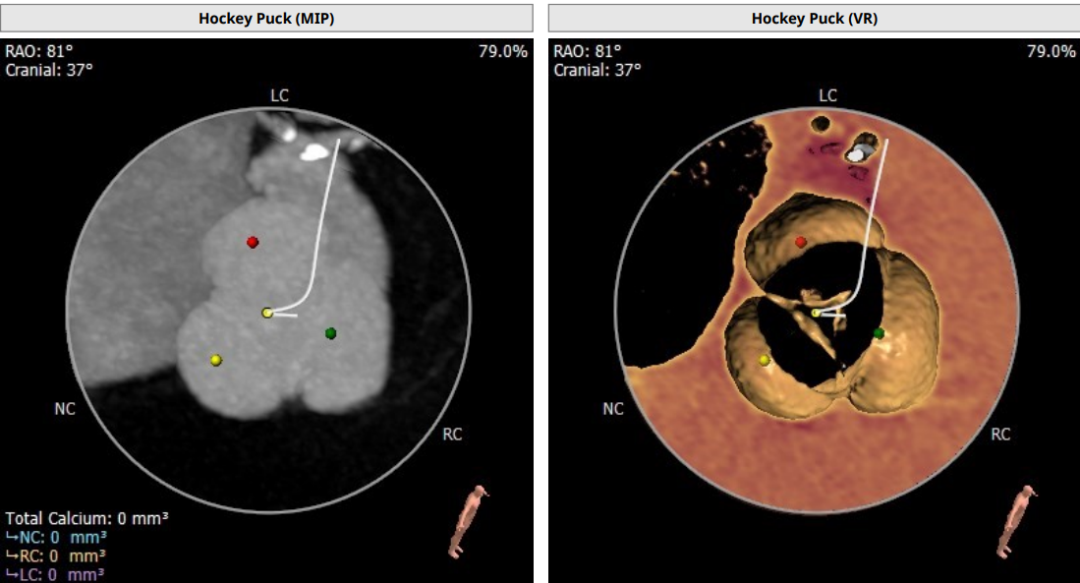

术前CT评估

Annulus Dimensions—25mm

LVOT—27.5mm

窦部:32.6*35.2*35mm

STJ—25.5mm

升主动脉存在明显增宽

重度主动脉瓣反流导致心室增大